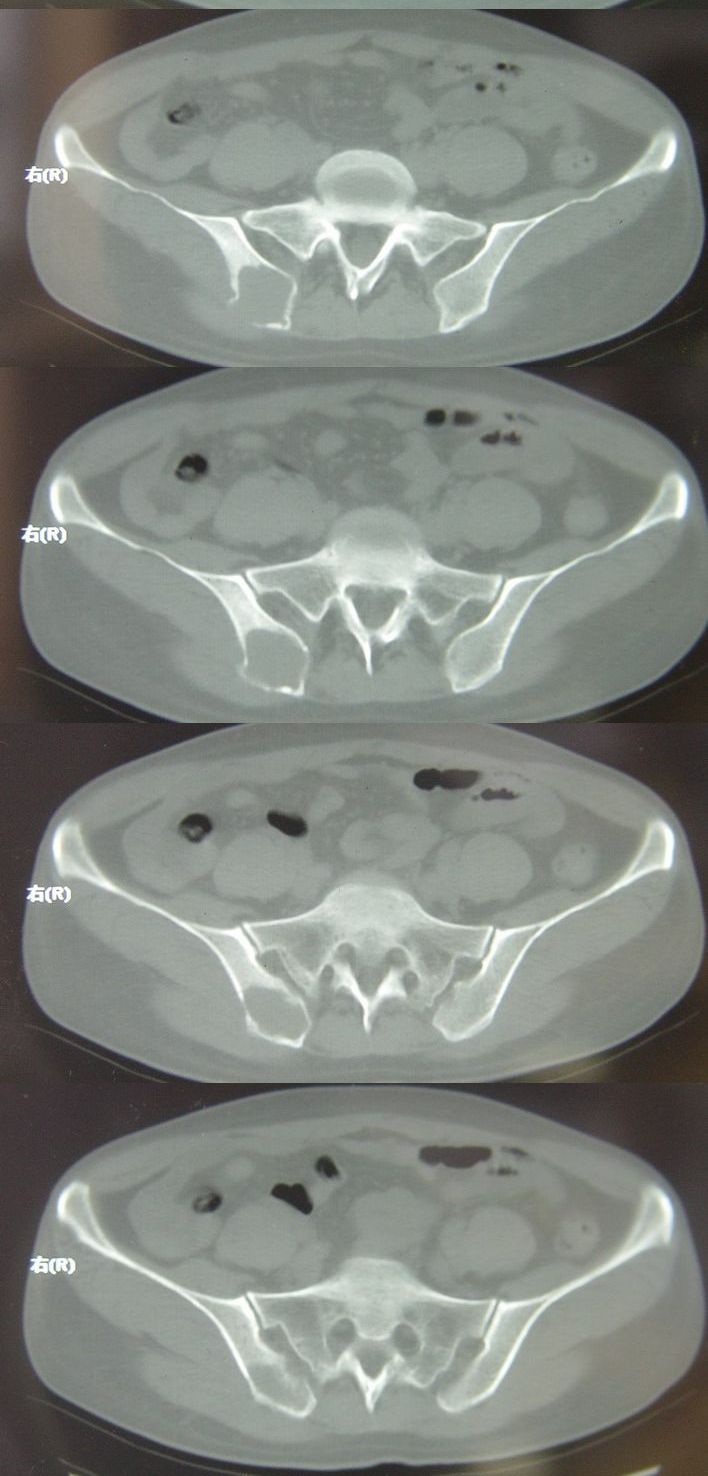

标题: CT13002:女,46岁。有子宫肌瘤手术史,现在出现右臀部向腿 [打印本页]

标题: CT13002:女,46岁。有子宫肌瘤手术史,现在出现右臀部向腿

考虑右侧髂骨骨囊肿可能性大。盆腔左侧可见混杂密度区,请告知手术方式,充盈肠管重扫除外占位性病变.

右侧髂骨膨胀性骨质破坏区 囊内密度尚均匀 骨巨细胞瘤可能性大 动脉瘤样骨囊肿不除外 建议mr观察囊内成分明确诊断 左侧附件区包裹性积液

据患者家属提示,曾在某医院检查说是卵巢有问题,患者这一次做ct增强,主要目的是排除卵巢病变,担心骨转移

右侧髂后上棘局限性囊状骨质破坏,大部分界清,似见轻度硬化边,内无分格及钙化,病灶上部局部显示模糊。考虑;骨巨细胞瘤可能大,不除外abc。另可见子宫肌瘤术后子宫缺如。

临床和影像学表现:女性患者46岁,有子宫肌瘤手术病史。影像所见可见残余宫颈部分,左右附件未见新生物;右髂骨翼后端囊状膨胀性骨破坏,囊性部分感觉有强化(楼主标上增强前后的ct值就很好了),未见明确的液—液平面,周边硬化不明显或轻度硬化。

分析:患者年龄46岁,没有明确外伤病史,病变呈膨胀性骨破坏,囊性部分未见明确的液—液平面,周边硬化不明显。综合分析该病例比较符合骨巨细胞瘤,不太符合动脉瘤样骨囊肿。

诊断:1、首先考虑骨巨细胞瘤;2子宫肌瘤术后改变